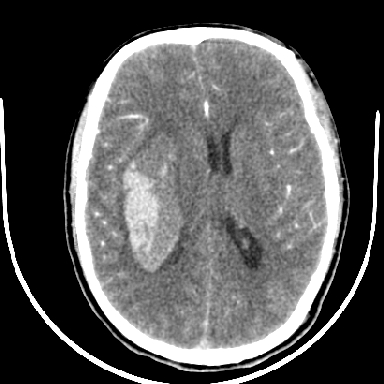

标题: CT6056:脑出血(血管畸形?) [打印本页]

标题: CT6056:脑出血(血管畸形?)

m 40突发头痛左侧偏瘫3小时

考虑高血压性脑出血,依据:

1是高血压性脑出血的好发部位,形态呈肾形,是高血压性脑出血的常见形状

2增强时占位效应加重了,考虑出血还没有停止

3病灶周围水肿不是太厉害,一般肿瘤出血水肿多非常明显

4病灶周围的‘软组织’影没有明显的强化

5至于脑血管畸形引起的出血,暂时没有看到明显的畸形血管影,也不太支持

支持右侧基底节脑出血

右侧基底节区脑出血.

支持右侧基底节区(主要为外囊区)原发性脑出血。

另附部分资料:“血液溢出血管外形成血肿,其内含有大量血红蛋白、血浆白蛋白,球蛋白,因这些蛋白对x线的吸收系数高于脑质,故ct呈现高密度阴影,ct值达40~90h,最初高密度灶呈非均匀一致性,中心密度更高,新鲜出血灶边缘不清。基底节区血肿多为“肾”型,内侧凹陷,外侧膨隆,因外侧裂阻力较小,故向外凸,其它部位血肿多呈尖圆形或不规则形”

术中抽出40ml陈旧血液,血肿底部似见一条索血管影